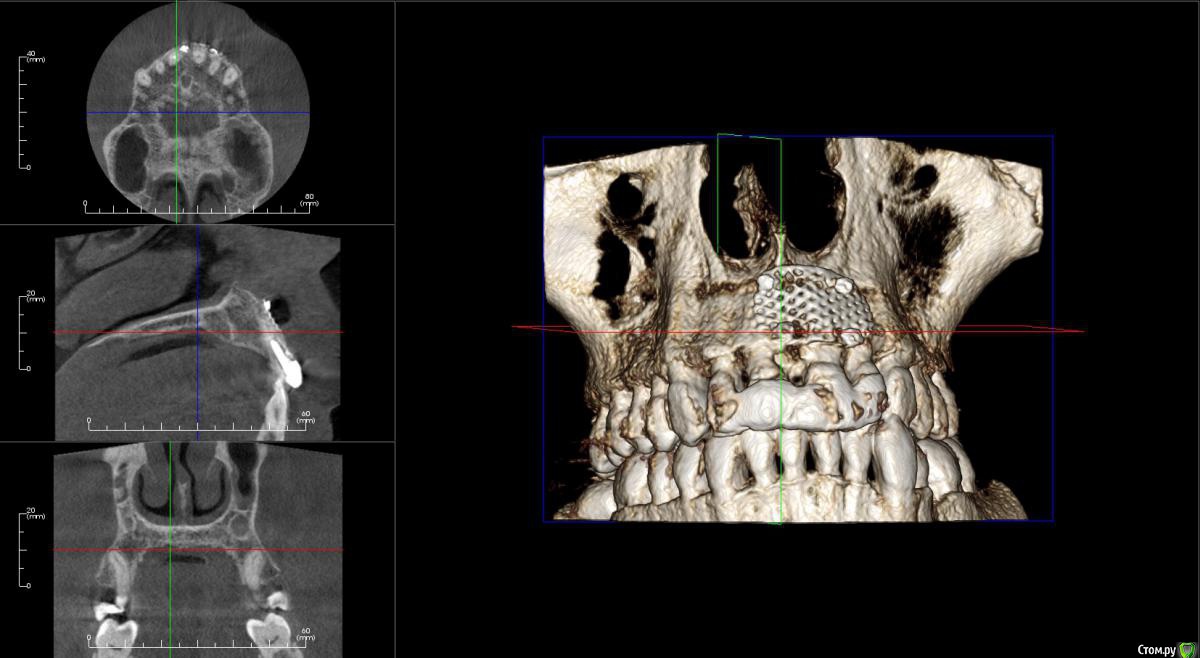

kamranchick Опубликовано 17 апреля, 2016 Поделиться Опубликовано 17 апреля, 2016 Пришел пациентДок привет, что то зуб шатается, можно ли его оставить, вот такие дела)как бы вы поступили бы? Ссылка на комментарий

dantist_movani Опубликовано 27 апреля, 2016 Поделиться Опубликовано 27 апреля, 2016 Пришел пациентДок привет, что то зуб шатается, можно ли его оставить, вот такие дела)как бы вы поступили бы?1)проверил бы на витальность2)Репозиция и шинирование орто ретейнером с жидкотекучим композитомпохожая ситуация была год назад, правда отлом кортикалки не столь значительный был. Ретейнер снял через 6 мес, все Ок, зуб не почернел♿, эод -8 в дуге, пац очень доволен Ссылка на комментарий